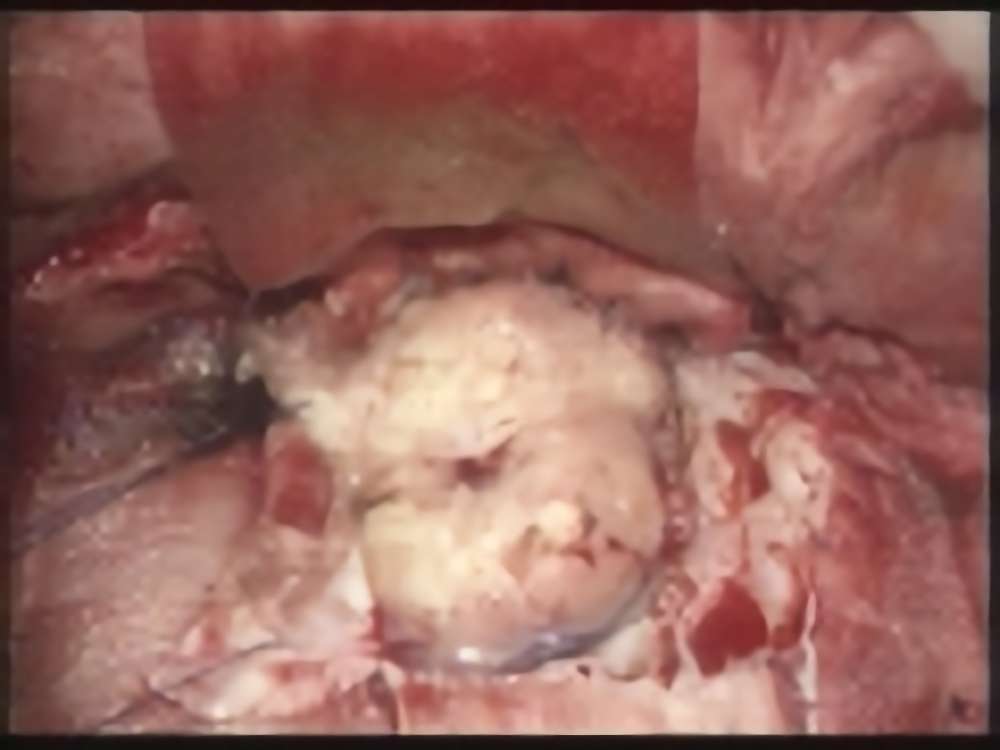

'14年6月

40代

海綿状血管腫

No.’14_104 手術前1

No.’14_104 摘出 前

No.’14_104 摘出 後